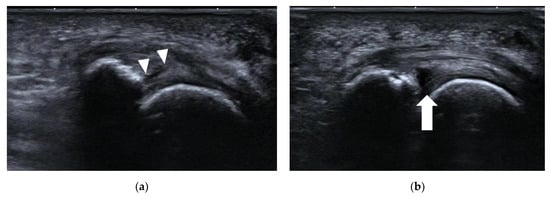

4.1.1. Plantar Plate Tear

| Plantar plate tear | 2nd MTP joint | discrete anechoic cleft or area of heterogeneous echotexture in the plantar plate |